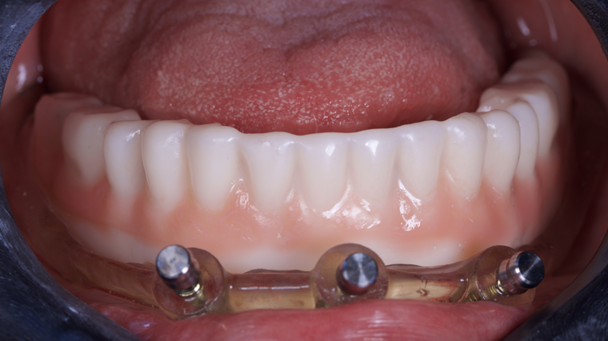

O guia foi fixado após estabilização em oclusão com a prótese superior. Após a retirada do guia de oclusão, foi fixada a guia de fresagem e instalação dos implantes, que foram instalados com torques superiores a 32N, o que permitiu a captura imediata da prótese provisória através do pilar de titânio e resina de fluxo.

O tempo do procedimento desde a anestesia até a finalização da prótese provisória foi de 2h10.